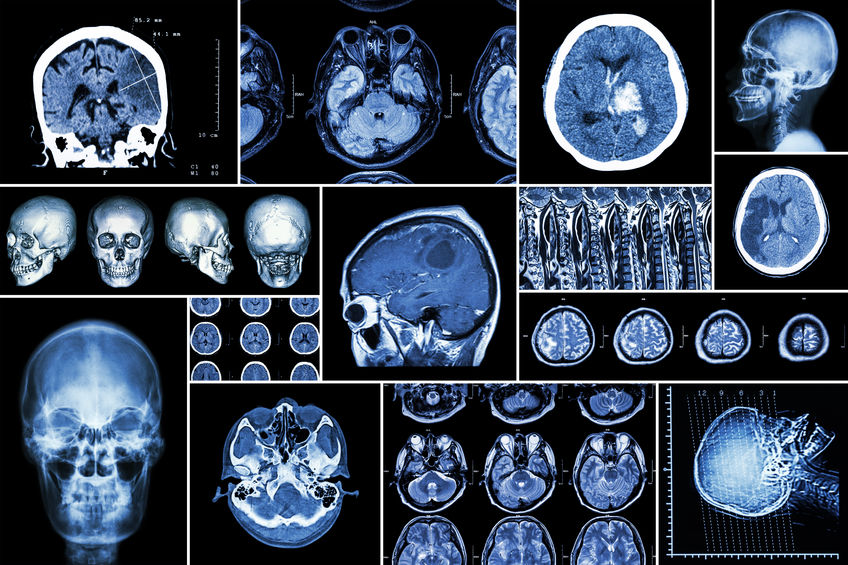

Because disorders of the nervous system are comparatively complex, they require a team of experts to ensure their proper diagnosis and treatment.

Patients at Memorial Health System of Southwest Oklahoma are cared for by a group of board-certified medical professionals, including neurologists and neurosurgeons. These specialists are supported by a team of nurses and other allied health professionals in their mission to provide patients with leading-edge neurological services.

Our neurosurgeons specialize in a multitude of conditions and procedures. View descriptions and animations of their specialties by navigating to the Conditions and Diseases or Treatment and Diagnostic Procedures pages.